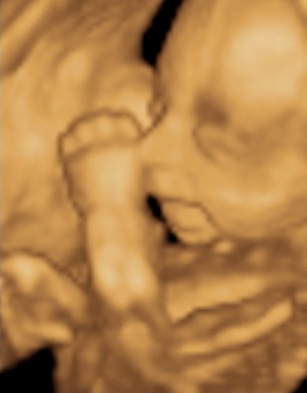

A 3D-s babafotok meg mindig lenyugoznek, nem birok betelni veluk. SZomoruan olvasom, hogy mennyi aprobb-nagyobb kellemetlensegetek van, de szerintem mindenki nagyon szuperul halad, ugyesek vagytok...le a kalappal foleg a dolgozok, vagy mar babasok elott! majd most teszek fel kepeket es is Azzurrarol, bar mar tobb, mint 5 hete keszultek, de ujabbak mar nem lesznek, es mivel kimaradtam abban az idoszakban, most potolom. Az tuti, hogy ezentul mindenkinek javasolni fogom a 4D-t ilyen koran is (22+1 hetesen voltunk), mert bar csimota ducibb volt az atlagnal es mar akkor volt rajta jo adagnyi izom (ez is a napi 1 l tej

), de egy sovanyabb baba is csodaszep szerintem...mindent el lehet mondani, csak azt nem, hogy csontkollekciok lennenek. Osszessegeben ugy nez ki, hogy ram hasonlit, de a szemoldokcsontja es a szaja az egy az egyben a parome...szerencsere...neki az sokkal szebb...remelem, haj-ugyben is ra ut majd